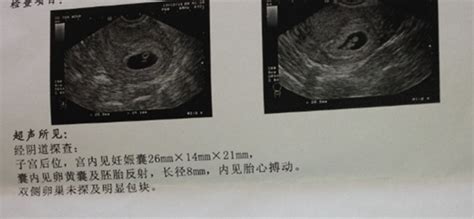

怀孕8个月b超图分析 8个月彩超图